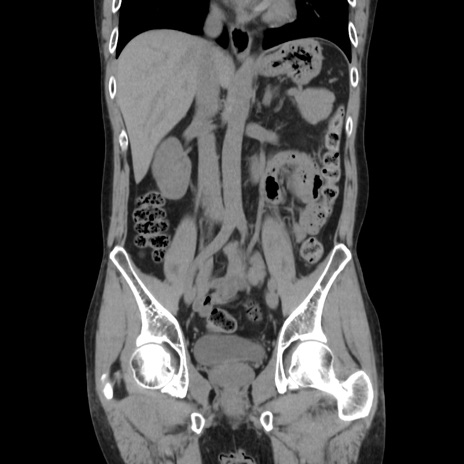

症例37(冠状断像)

【症例】40歳代 男性

【主訴】腹痛

【現病歴】4時間ほど前に電車に乗車中に臍部上より腹痛出現。徐々に増悪し起立困難となり、救急外来受診。生ものは数日食べていない。今朝お雑煮を食べた。

【身体所見】BT 36.8℃、BP 117/84mmHg、HR 91/min、SpO2 97%、苦悶様、腹部:臍上部広範囲圧痛あり、反跳痛±

【データ】WBC 8100、CRP 0.03